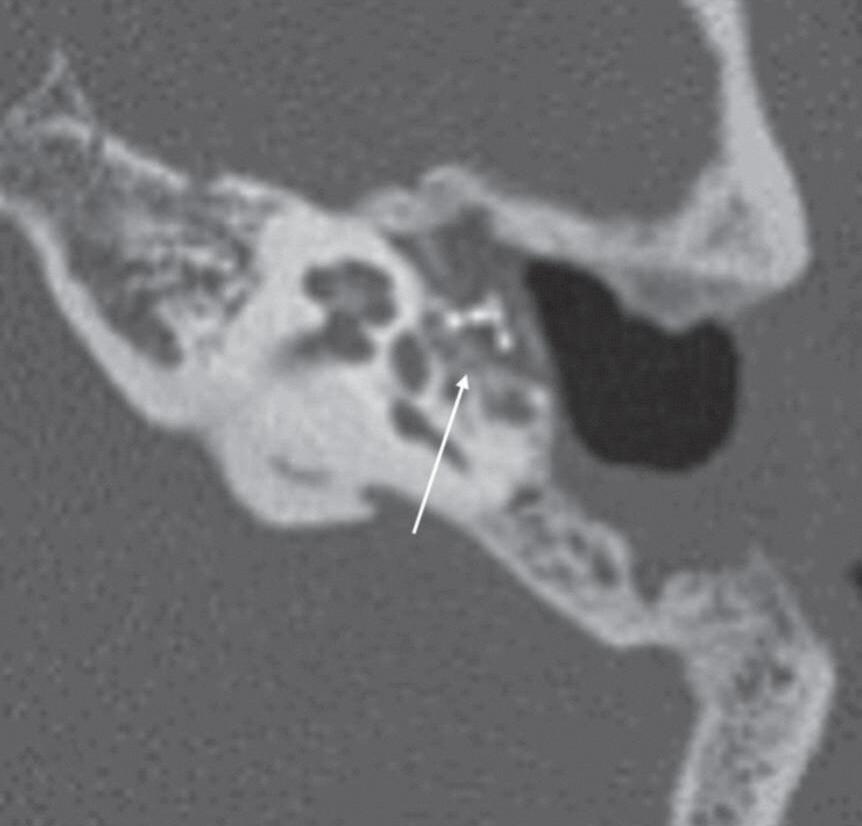

1-4. Prótese de estribo deslocada; P.O.R.P. (a) TC sagital oblíquo: prótese de estribo deslocada (seta). (b) TC axial oblíquo: P.O.R.P. se articulando com o estribo. Mastoidectomia com cavidade aberta.